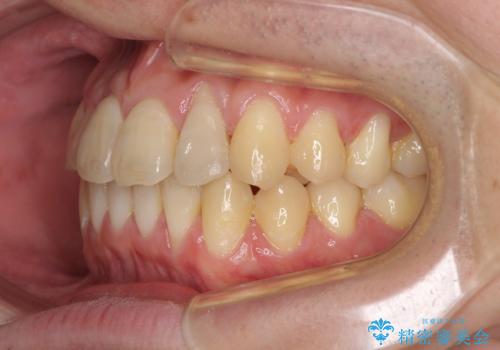

前歯のクロスバイト インビザラインによる矯正治療

- 上下のクロスバイトと前歯のデコボコを気にして来院された患者様です。

インビザラインを用い、IPR(歯と歯の間を削る)と歯列全体を拡大させることで、歯並びを整えていくこととしました。

奥に位置していた上の前歯が下の前歯を乗り越える際、奥歯でものを咬むことができず、辛い時期が続きました。